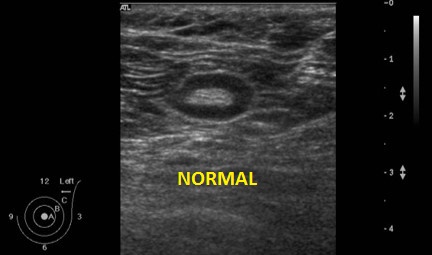

En el estudio el diagnóstico puede llevar a resultados falsos-positivos al confundir nodos linfáticos cervicales y sobretodo nódulos tiroideos con este tipo de tumor y diagnosticar otras patologías con la que nos atañe, por contra también se puede dar un diagnóstico erróneo al confundir el adenoma con un nódulo tiroideo en el contexto de bocio multinodular, menos habitual, pero muy a tener en consideración es el adenoma paratiroideo ectópico, figura que junto con el BMN puede conducir a la/el Radiólogx a Falsos-Negativos, donde se puede no diagnosticar esta patología interpretando que es otro tipo de lesión.

Te pido ahora que observes aténtamente la imagen 7 y la imagen 8 y en las lesiones marcadas con flechas amarillas. En la imagen 7 puedes ver imágenes nodulares en ambos lóbulos tiroideos, son nódulos de los que habitualmente encontramos en un bocio multinodular, compara ahora con la imagen de la imagen 8, así a bote pronto, ¿Te llama algo la atención?…mira bien las imágenes…tómate un momento, no sigas leyendo…